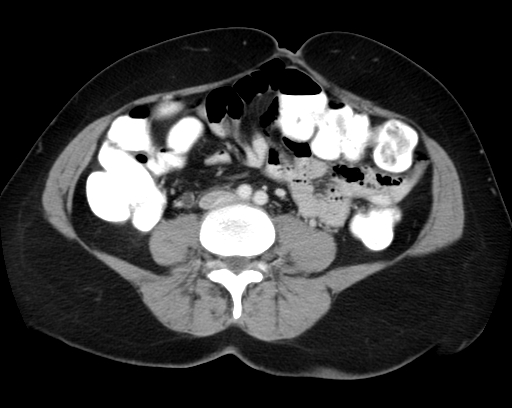

What's the Diagnosis?